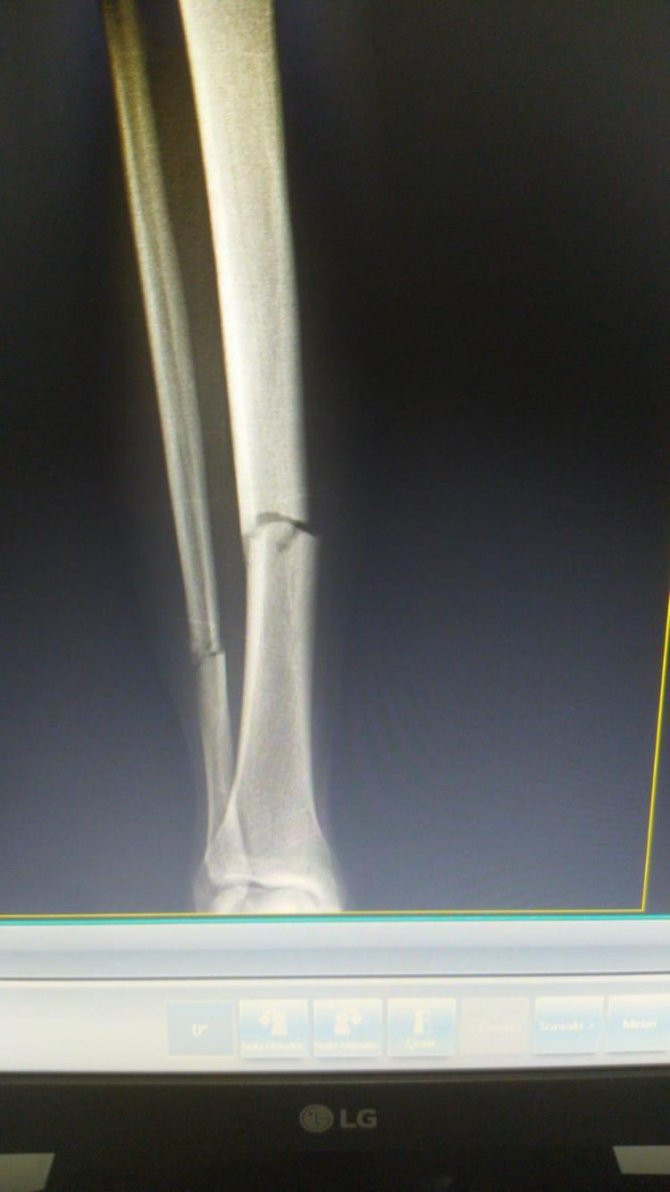

KAVAL KEMİĞİNDE 2 KIRIK TESPİT EDİLDİ

Karşılaşmanın 15. dakikada Skoda ile çarpışan ve acılar içerisinde yerde kalan Muslera, hastaneye götürüldü. Galatasaraylı futbolcular ve teknik heyet, takımın en önemli isminin durumunu merak dolu gözlerle takip etti. Uruguaylı file bekçisinin kaval kemiğinde 2 kırık tespit edildi. Sezonu kapattığı öğrenilen Uruguaylı file bekçisinin, yarın ameliyat olacağı kaydedildi.